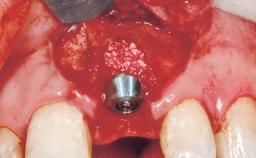

Immediate Flapless Placement of an Implant in a Maxillary Right Lateral Incisor Site

This 43-year-old male patient, a non-smoker, came to our practice because of a fracture of tooth 12 caused by a bicycle accident. Due to the combined para- and infrabony crown and root fracture, tooth extraction, and subsequent implant placement were suggested to the patient as the therapy of choice. The patient had high esthetic expectations with regard to the treatment outcome and asked for an immediate fixed provisional restoration. His individual esthetic risk profile summed up to a medium esthetic risk.

Placement Protocol Immediate implant placement

Socket Morphology Single-root socket

Socket Integrity Sufficient, with intact bone walls

Bone Volume Sufficient, with intact walls